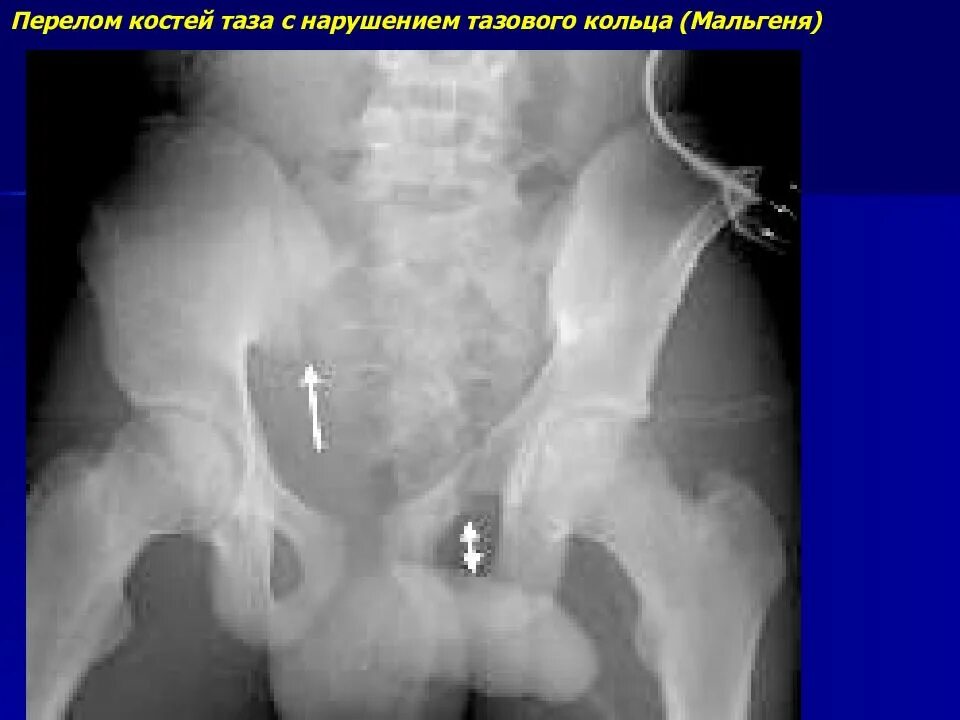

Разрыв крестцово подвздошного сочленения